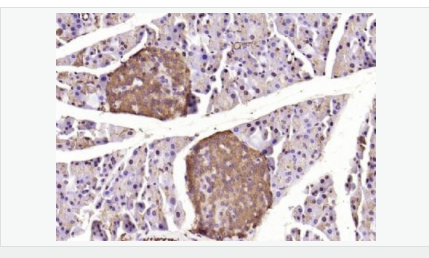

| 產(chǎn)品應(yīng)用 | WB=1:500-2000 ELISA=1:5000-10000 IHC-P=1:100-500 IHC-F=1:100-500 Flow-Cyt=1ug/Test ICC=1:100 IF=1:100-500 (石蠟切片需做抗原修復(fù)) not yet tested in other applications. optimal dilutions/concentrations should be determined by the end user. |

| 產(chǎn)品介紹 | Caspase 9 (also known as ICE like apoptotic protease 6 (ICE LAP6), apoptotic protease Mch6, and apoptotic protease activating factor 3 (Apaf3)) is a member of the peptidase family C14 that contains a CARD domain. This caspase is active as a heterotetramer and has been reported to have two isoforms. ProCaspase 9 has been reported to be approximately 47 kD. This caspase is present in the cytosol and, upon activation, translocates to the mitochondria. Caspase 9 is involved in the caspase activation cascade responsible for apoptosis execution and cleaves/activates Caspase 3 and Caspase 6. Caspase 9 is inhibited by the dominant negative isoform, BclXL, cIAP1, cIAP2, XIAP, and Livin. This caspase becomes activated when recruited to Apaf1/cytochrome c complex, and following cleavage by Apaf1, granzyme B, Caspase 3, possibly Caspase 8 and Caspase 10 into large p37 and small p10 subunits. Caspase 9 intereacts with BIRC7 and has been shown to cleave PARP and vimentin. Function: Involved in the activation cascade of caspases responsible for apoptosis execution. Binding of caspase-9 to Apaf-1 leads to activation of the protease which then cleaves and activates caspase-3. Proteolytically cleaves poly(ADP-ribose) polymerase (PARP). Isoform 2 lacks activity is an dominant-negative inhibitor of caspase-9. Subunit: Heterotetramer that consists of two anti-parallel arranged heterodimers, each one formed by a 35 kDa (p35) and a 10 kDa (p10) subunit. Caspase-9 and APAF1 bind to each other via their respective NH2-terminal CED-3 homologous domains in the presence of cytochrome C and ATP. Interacts (inactive form) with EFHD2. Interacts with HAX1. Interacts with BIRC2/c-IAP1, XIAP/BIRC4, BIRC5/survivin, BIRC6/bruce and BIRC7/livin. Tissue Specificity: Ubiquitous, with highest expression in the heart, moderate expression in liver, skeletal muscle, and pancreas. Low levels in all other tissues. Within the heart, specifically expressed in myocytes. Post-translational modifications: Cleavages at Asp-315 by granzyme B and at Asp-330 by caspase-3 generate the two active subunits. Caspase-8 and -10 can also be involved in these processing events. Phosphorylated at Thr-125 by MAPK1/ERK2. Phosphorylation at Thr-125 is sufficient to block caspase-9 processing and subsequent caspase-3 activation. Similarity: Belongs to the peptidase C14A family. Contains 1 CARD domain. SWISS: P55211 Gene ID: 842 Database links: Entrez Gene: 842 Human Entrez Gene: 12371 Mouse Omim: 602234 Human SwissProt: P55211 Human SwissProt: Q4FJK5 Mouse Unigene: 329502 Human Unigene: 88829 Mouse Unigene: 32199 Rat Important Note: This product as supplied is intended for research use only, not for use in human, therapeutic or diagnostic applications. Caspase-9半胱氨酸蛋白酶家族成員之一,又稱ICE-Lap6(ICE Like apoptotease 6)參與細胞凋亡過程和細胞因子的加工過程,在許多胚胎和成人組織中都有分布。此抗體主要用于腫瘤研究。 |